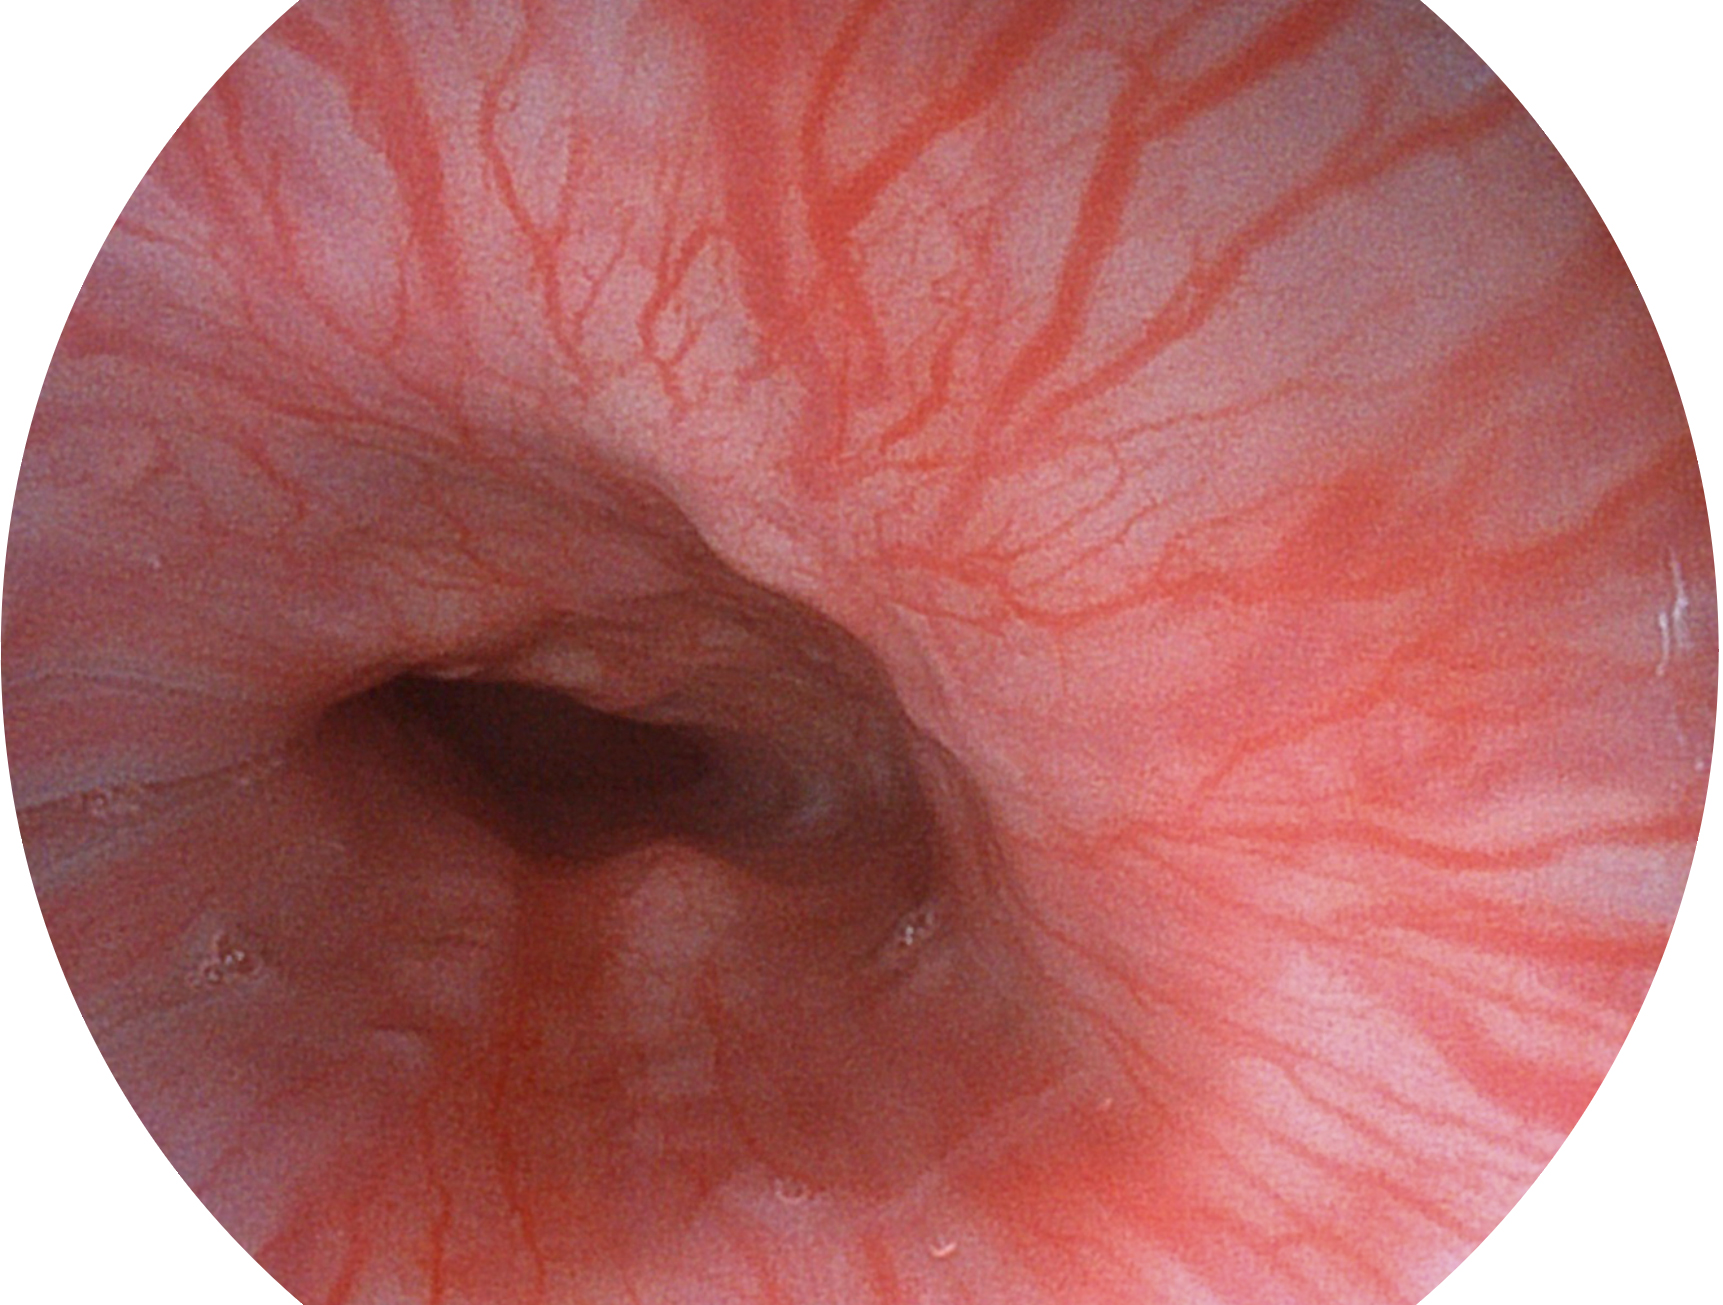

DB中国旗舰官方网站新开发的内镜染色技术,主要是基于多波长LED 光源的开发,VLS-55Q 四波长LED 光源是由四个不同颜色的LED光按照相应照明模式所规定的特定发光比例进行合束后形成,合束后形成的照明光的光谱由红光、绿光、蓝光及蓝紫光这四个不同的波段范围构成。具有更高光谱自由度,通过光谱比例的控制,实现了聚谱成像技术,英文全称为“Spectral Focused Imaging, SFI”,缩写为“SFI”和光电复合染色成像技术,英文全称为“Versatile Intelligent Staining Technology, VIST”,缩写为“VIST”。